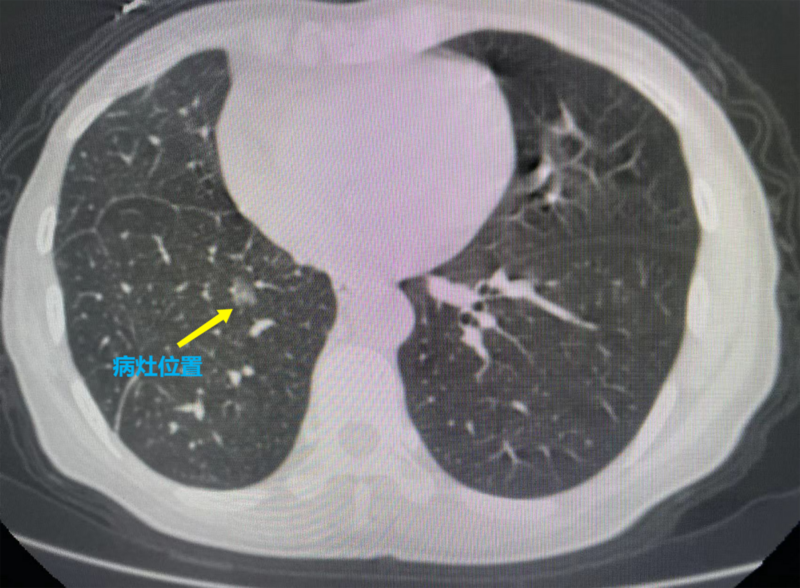

李某平時(shí)一直身體健康,2020年11月在市人民醫(yī)院健康管理中心進(jìn)行胸部CT體檢時(shí),發(fā)現(xiàn)右下肺有1個(gè)磨玻璃結(jié)節(jié),大小為8mm*6mm,當(dāng)時(shí)醫(yī)囑予以隨訪觀察。2022年8月初,李某在我院門診復(fù)查胸部CT提示右下肺的磨玻璃結(jié)節(jié)為10mm*7mm,較前增大,密度稍較前增強(qiáng),略呈混雜樣磨玻璃改變,遂入住胸心外科進(jìn)一步治療。

手術(shù)當(dāng)天,胸心外科手術(shù)團(tuán)隊(duì)在醫(yī)學(xué)影像科、麻醉科等科室的配合下,為李某進(jìn)行了微波消融手術(shù)。先由影像科技師進(jìn)行CT平掃,確定病灶位置及進(jìn)針的方向及深度,胸心外科醫(yī)生在李某體表定位點(diǎn)局麻后取一次性微波消融針逐層穿刺,CT再次掃描確保消融針到達(dá)準(zhǔn)確位置后用導(dǎo)線連接消融機(jī),選定恰當(dāng)功率,算好時(shí)間,開啟消融,同時(shí)術(shù)中給予心電監(jiān)護(hù)等監(jiān)測(cè),消融過(guò)程順利。消融后再次掃描CT可見(jiàn)消融范圍完全覆蓋右下肺結(jié)節(jié),手術(shù)治療成功!術(shù)后幾日復(fù)查CT,可見(jiàn)李某的肺結(jié)節(jié)變成“條索影”了,原來(lái)的結(jié)節(jié)已經(jīng)完全消失!李某后續(xù)治療定期復(fù)查即可。神奇的手術(shù)讓李某非常激動(dòng),“不開刀也可以根治腫瘤,現(xiàn)在的科技真發(fā)達(dá),以后一定讓更多的“結(jié)友們”知道這個(gè)好消息!”